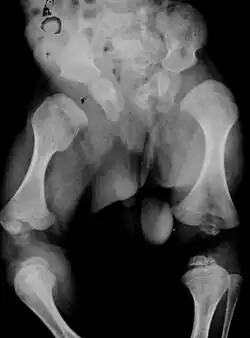

Im Röntgenbild der Wirbelsäule finden sich eine Platyspondylie, ventral zugespitzte Wirbelkörper und bei Säuglingen können vertikale Spaltwirbel vorkommen. Die Beckenschaufeln sind breit mit Unterentwicklung der unteren Anteile des Darmbeins, erheblich verbreiterte, plumpe und kurze Schenkelhälse, verkürzte und metaphysär aufgetriebene Röhrenknochen.[1]

Große Epiphysen und spätes Auftreten des Oberschenkelkopfes im 2. bis 3. Lebensjahr sind weitere Kriterien[2], sowie Megaepiphysen im Knie- und Hüftgelenk.[6]